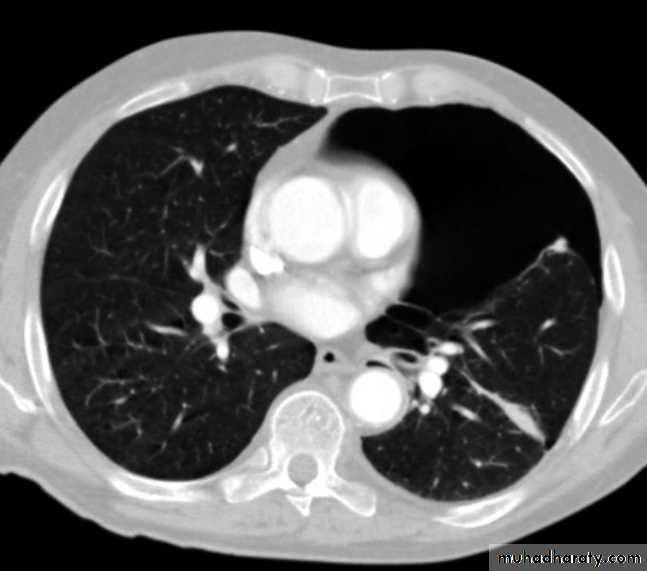

CT abdomen

Secondary metastasis in the liver

Multiple rounded hypo density areas of different density , shape & different size .

Pattern of enhancement is either uniform , target or bulls eye pattern .

Hepato megaly .

Secondary metastasis within the liver